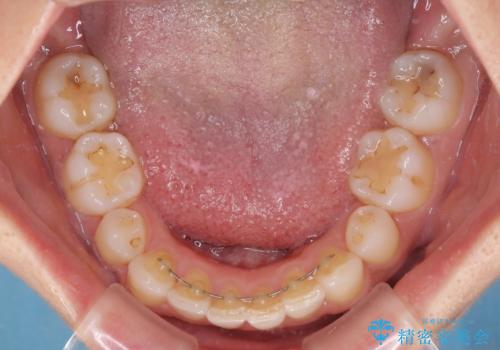

毎日22時間の装着時間を守ってくださいましたが、ハイペースにマウスピースを交換することなく、慎重に治療を進めてくださったので、治療期間はやや長くなりました。

臼歯部も含め、叢生が綺麗に改善され、患者様には大変満足していただきました。